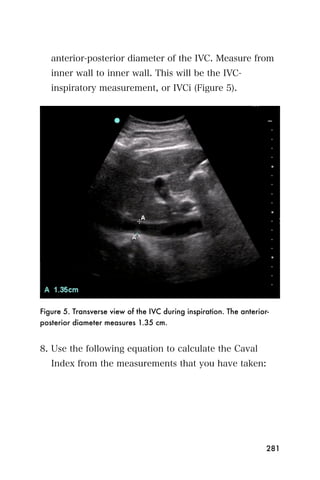

9. The age of the baby appears at the bottom of the

ultrasound screen (Figure 8).

113

Figure 8. CRL measured with calipers. Gestational age calculation